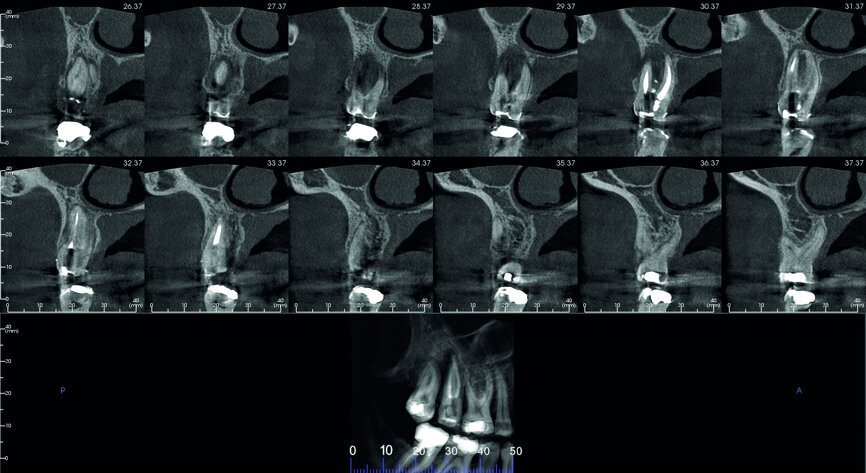

Fig. 5: Pre-op CBCT scan, sections.

A 47-year-old male patient in a good medical condition and a non-smoker was referred to our dental practice for endodontic retreatment of the right maxillary second molar. The dental history revealed that the tooth had been endodontically treated three months before because of acute pulpitis. After the treatment, the patient complained of pain on chewing. Antibiotics and a non-steroidal anti-inflammatory drug were prescribed, but the pain remained. After a month, a sinus tract appeared. The tooth was retreated in another practice without success. The clinical inspection revealed the presence of a sinus tract near the apical region of tooth #17. The tooth had been prepared for a full crown, but was without even a temporary crown, and the access cavity had been closed with temporary filling material. Cracks were evident on the buccal and mesial surfaces. Periodontal probing showed a deep pocket (> 12 mm) on the distal aspect of the root trunk (Figs. 1 & 2). The periapical radiograph showed a radiolucency between the roots of the second and third molars. The radiographic appearance of the endodontic treatment was good, without clear evidence of periapical radiolucencies (Fig. 3). A perforation of the pulp chamber floor was suspected. A CBCT scan was performed (Figs. 4–7), and it confirmed the suspicion of perforation, along with the presence of a large periradicular radiolucency and an unfavourable root shape.